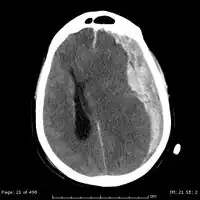

Subdural hematomas occur most often around the tops and sides of the frontal and parietal lobes.[9][10] They also occur in the posterior cranial fossa, and near the falx cerebri and tentorium cerebelli.[9] Unlike epidural hematomas, which cannot expand past the sutures of the skull, subdural hematomas can expand along the inside of the skull, creating a concave shape that follows the curve of the brain, stopping only at dural reflections like the tentorium cerebelli and falx cerebri.

On a CT scan, subdural hematomas are classically crescent-shaped, with a concave surface away from the skull. However, they can have a convex appearance, especially in the early stages of bleeding. This may cause difficulty in distinguishing between subdural and epidural hemorrhages. A more reliable indicator of subdural hemorrhage is its involvement of a larger portion of the cerebral hemisphere. Subdural blood can also be seen as a layering density along the tentorium cerebelli. This can be a chronic, stable process, since the feeding system is low-pressure. In such cases, subtle signs of bleeding—such as effacement of sulci or medial displacement of the junction between gray matter and white matter—may be apparent.

Fresh subdural bleeding is hyperdense, but becomes more hypodense over time due to dissolution of cellular elements. After 3–14 days, the bleeding becomes isodense with brain tissue and may therefore be missed.[22] Subsequently, it will become more hypodense than brain tissue.

Acute bleeds often develop after high-speed acceleration or deceleration injuries. They are most severe if associated with cerebral contusions.[9] Though much faster than chronic subdural bleeds, acute subdural bleeding is usually venous and therefore slower than the arterial bleeding of an epidural hemorrhage. Acute subdural hematomas due to trauma are the most lethal of all head injuries and have a high mortality rate if they are not rapidly treated with surgical decompression.[24] The mortality rate is higher than that of epidural hematomas and diffuse brain injuries because the force required to cause subdural hematomas tends to cause other severe injuries as well.[25]